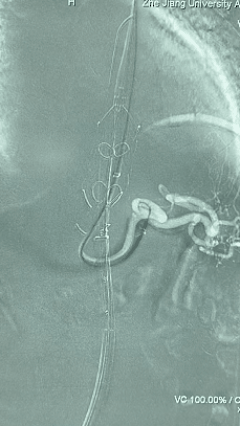

6. 解除束径,打开近端后释放,经肱动脉长鞘超选支架外分支,并进一步超选右侧肾动脉,交换加硬导丝,送入覆膜支架6*50mm和7*60mm各一枚,并予以球囊后扩张,手推造影显影良好。

7. 经长鞘重新选入左侧外分支,并超选进左肾动脉,沿导丝送入外周血管覆膜支架7*60mm一枚,并予以球囊后扩张,手推造影显影良好。

8. 从右侧股动脉入路送入腹主支架AB-24-12-110-S,近端重叠胸腹主动脉支架远端,调整好支架位置后释放。

9. 经左股动脉送入导丝导管,超选进腹主动脉支架短腿内,后沿导丝送入髂支,同理,右侧沿导丝送入髂支并释放,使用先健顺应性球囊后扩各支架连接处及支架近远端,最后通过预留导管向瘤腔注入人纤维蛋白粘合剂数支,造影显示分支通畅。